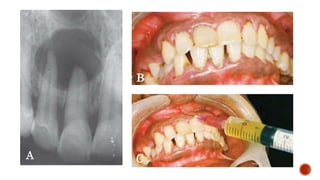

Anterior teeth is involved in infarction is the

A

C

B